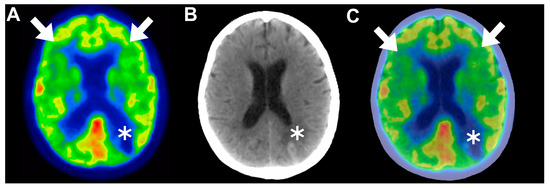

4.3.1. First Attempt to Detect Neurotoxicity via Brain [18F]FDG PET

4.3.2. Global Brain Hypometabolism

4.3.3. Frontal Predominant Encephalopathy

4.3.4. Functional Alterations Associated with Neurotoxicity